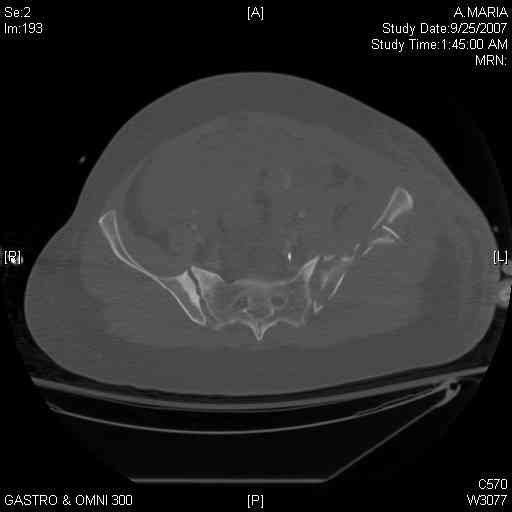

Thanks. I probably didn't include enough images on the CT, but it didn't look to me like an SI screw would be of value except into S2, which I am not

comfortable placing. I will post finals if the neurosurgeons let me operate on her. ICPs still a problem.